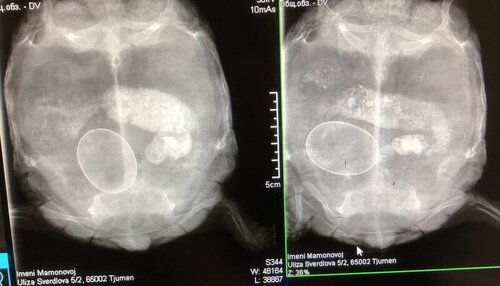

Олька-72 Ваше имя: Пуговка Локация: Тюмень Опубликовано: 1 октября 2022 Опубликовано: 1 октября 2022 Тюмень. 34 года. Среднеазиатская сухопутная. Террариум 100*60. Оборудование: УФ лампа 10%, греющая лампа, работают не менее 12 часов в день Грунт: Кукурузный наполнитель Еда и подкормки: Корм Sera herbivor, витамины рептилайф, Beaphar Turtle vit, Tetra reptocal. овощи, фрукты, одуванчики, листья салата. 6 лет, точный вес 945гр. и длина 15см. Непроходимость яиц. Ветеринарная клиника Имени Евгении Мамоновой, Делали несколько раз рентген, прописали вазелиновое масло, уколы для стимулирования родов. Помогите, пожалуйста, что делать, если у черепахи внутри застряло яйцо, сама родить не может, находится яйцо уже больше месяца, боюсь, что может начаться перитонит. Часть яйца видно, когда поднимаешь хвост, цвет скорлупы уже изменился на желтоватый. До этого было много кладок, но так же со стимулированием родов.